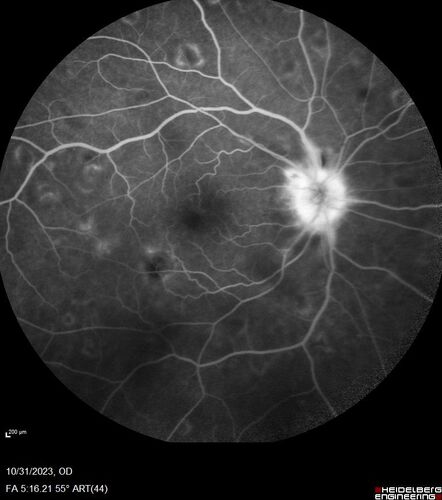

Serpiginous choroiditis in the right eye

68 year old female with spots in vision in the right eye for 2 months.  She has a history of MS.  The vision is 20/32 in both eyes.  She was treated with high dose steroids and transitioned to methotrexate and the right eye quieted  down.